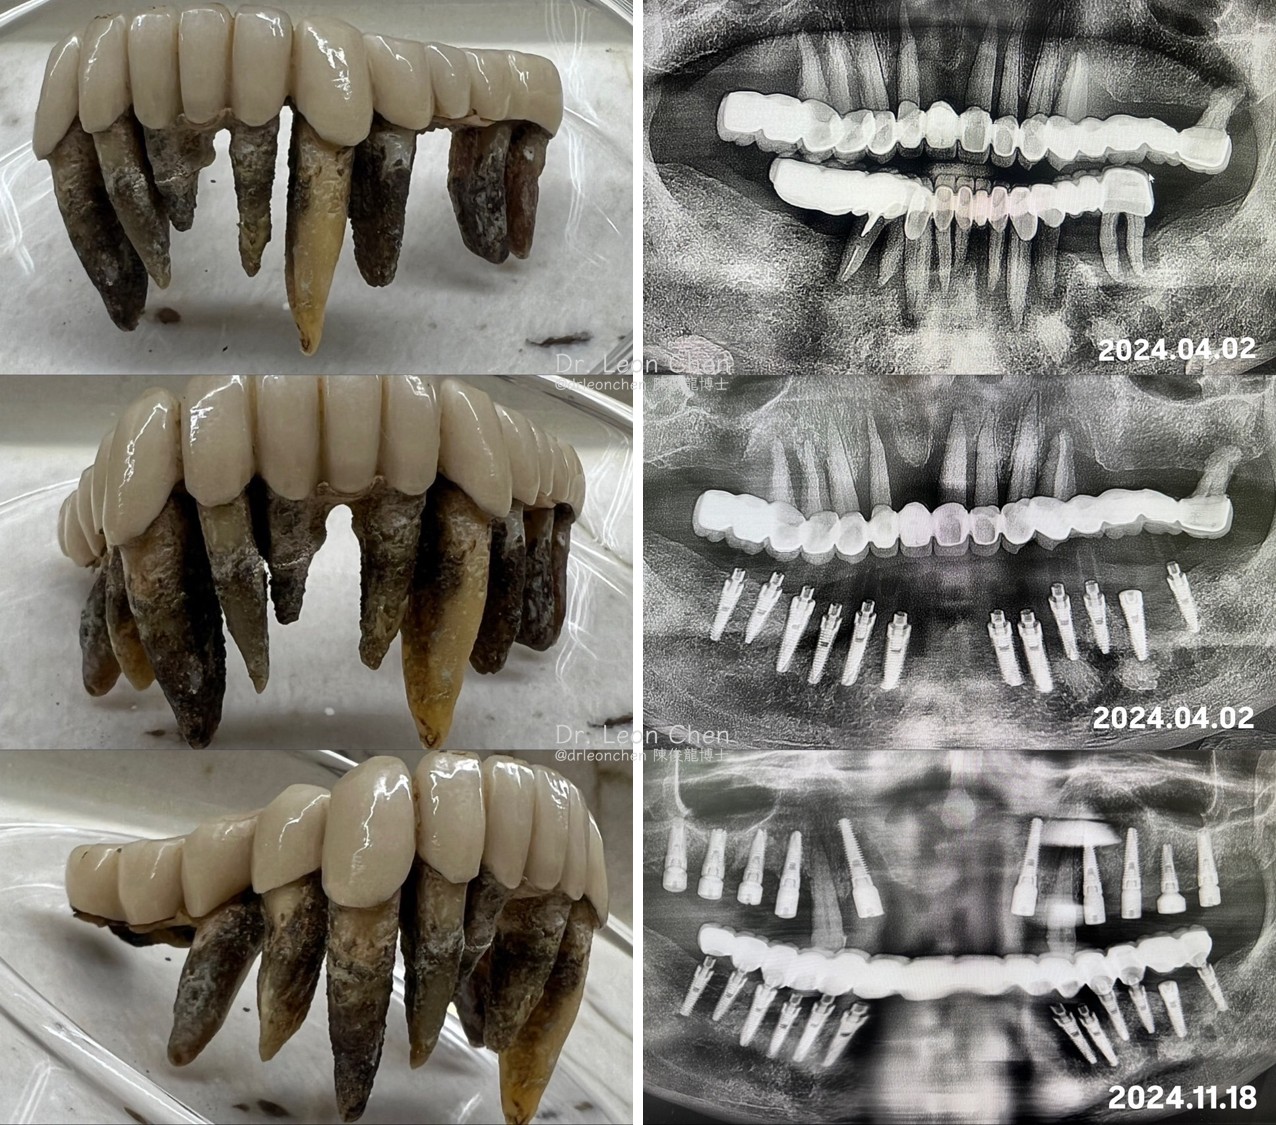

精奈創一鑽植牙系統團隊|重度牙周炎患者

這位患者原本牙周炎非常嚴重,在陳博士的治療下,仍能做到即拔即植。

唯有良好初期穩定性(primary stability)的植體,才能一次植多顆,完成全口5(6) in 1植牙。

患者年紀也不小了,能在短時間內完成下顎植牙,避免漫長等待與反覆手術的折磨,甚至在手術後還希望能盡快進行上顎的植牙。

※這就是「陳俊龍博士整套 LEONS Concept 精奈創一鑽植牙」技術的優勢,手術少、恢復快,讓患者輕鬆跨越過去覺得不可能的關卡。